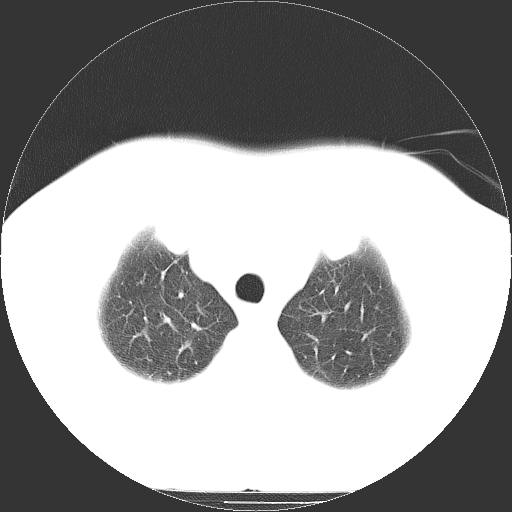

标题: CT21804:男,65岁,咳嗽、咳痰、发热5天。 [打印本页]

男,65岁,咳嗽、咳痰、发热5天。

支持慢性支气管炎伴感染,双侧少量胸腔积液.

两肺间质纤维化,支扩合并感染,双侧胸腔积液

慢性支气管炎并感染,支扩,双侧少量胸腔积液.